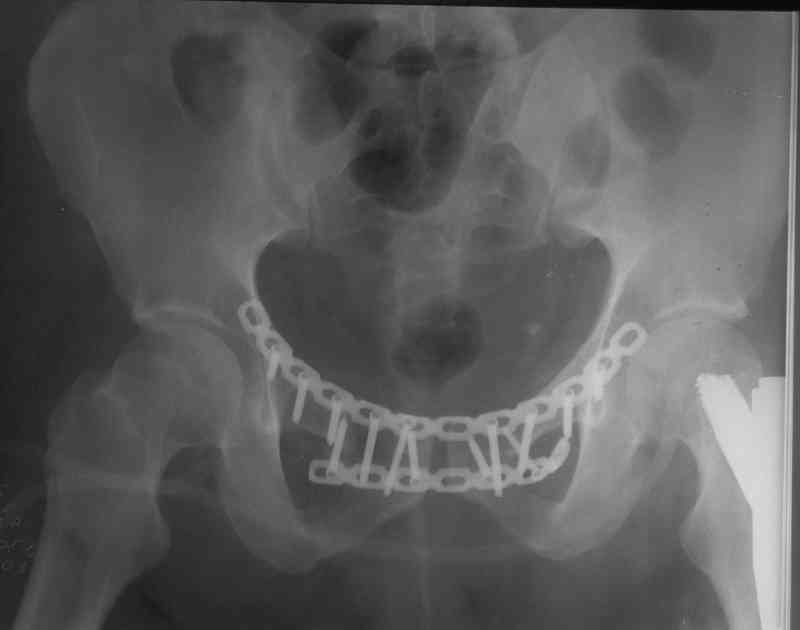

пациента с вторично заживающей раной после лапаротомии забили гвоздь и только через три недели (после заживления лапаратомной раны) фиксировали переднее полукольцо пластинами. Это тучный пациент лечение в аппарате не перенес бы.

Пластина спереди (на лонные кости) открыто и каннюлированные винты с обеих сторон сзади - закрыто.

Предварительная репозиция может быть достигнута при помощи аппарата.